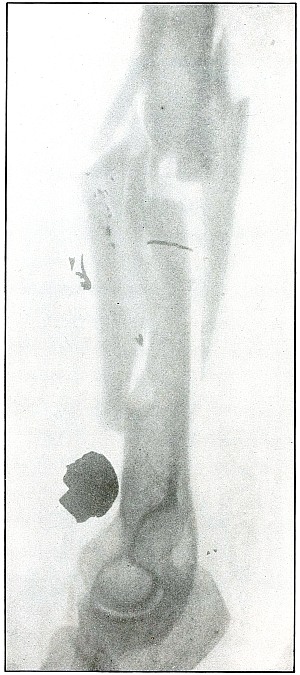

Plate 52.

[Pg 115]

Rifle—Plate 52.

LOWER EXTREMITY.

Gunshot Fracture of the Upper Shaft of the Femur.

The course of the bullet was anteroposterior and pierced the axis

of the shaft of the femur with three radiating lines of fracture,

resulting from the perforating action of the bullet striking the bone

at long range and with greatly reduced energy.

This plate shows the lateral separation of large fragments,

which is typical of gunshot wounds of long range.

Such wounds are usually not infected.

Emergency treatment is antiseptic dressing and coaptation with

extension and temporary splint, so that it may support the bone for

transportation and may be easily removable at place of continued

treatment.

In these cases with lateral separation of fragments, it is imperative

to supplement extension with pressure in a line perpendicular to the

long axis of the femur.